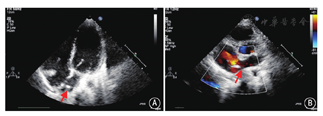

选用不同型号的ASD或卵圆孔未闭(PFO)封堵器(由厂商提供,专供示教演示使用)在各缺损处进行封堵测试,观察封堵器置入后的形态、各缺损的覆盖情况以及与二尖瓣环的距离(图3),最后选定一枚置入后形态良好、尽可能覆盖全部缺损同时不压迫二尖瓣的封堵器,记录封堵的型号和置入位置。